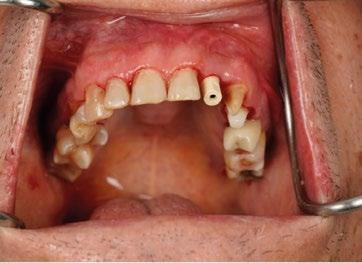

El primero de nuestros pacientes, de 32 años, había perdido su incisivo central superior derecho a los 12 años y el segundo, de 29 años, había perdido su incisivo lateral superior izquierdo en un accidente de tráfico ocurrido siete años antes. (Figura 4)

Transcurrido el periodo de cicatrización, se procedió en un segundo tiempo quirúrgico a retirar el tornillo de cierre y a colocar un pilar estándar —habitualmente empleado en prótesis híbridas—, utilizándolo como pilar de cicatrización. (Figura 6)

Ya estabilizados los tejidos, se procedió a la toma de impresiones y a la rehabilitación de ambos incisivos mediante coronas metalcerámicas. Para ello se utilizó el pilar para unitarios diseñado por Torsten Jemt, que, junto con un dispositivo también desarrollado ad hoc, permitía atornillar el pilar ejerciendo un cierto contratorque que hoy en día sabemos innecesario en un implante integrado. (Figura 7)

Durante los 17 años siguientes, ambos implantes funcionaron de manera satisfactoria, cumpliendo correctamente su cometido tanto en el plano funcional como en el estético. Sin embargo, en 2005 fue necesario sustituir la corona del incisivo central debido a una nueva fractura. Para ello se recurrió a la tecnología disponible en ese momento: se diseñó un pilar en resina acrílica, que posteriormente fue escaneado y fresado en zirconio (Procera), sobre el cual se confeccionó una corona totalmente cerámica en alúmina. (Fig. 9 y 10)

También la corona del lateral se volvió a rehacer en el año 2025 al mismo tiempo que se restauraron 23 y 24, utilizando la tecnología disponible hoy en día mediante impresión digital. (Fig. 12 a 16)